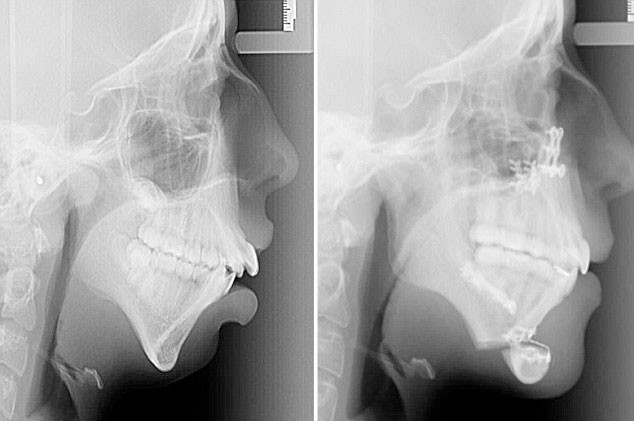

Yüzündeki doğuştan gelen deformasyon düzeltilen 20 yaşındaki Ellie Jones, şimdi güzellik kraliçesi olmak için yarışıyor. Daily Mail'de yayınlanan habere göre 8 yaşından beri çenesi gelişmeyen Ellie'nin dişleri biçimsiz bir şekilde büyümüştü. Bu durum 14 yaşındayken diş telleri taktırmak için dişçiye gittiğinde anlaşıldı.

Çenesi ve yüzünü düzelttirmek için 6 yıl tedavi gören genç kadının hayatı tamamen değişti. Kendi deyimiyle bir zamanların "çirkin ördek yavrusu" güzel bir kuğuya dönüştükten sonra Galler güzeli olmak için yarışıyor.